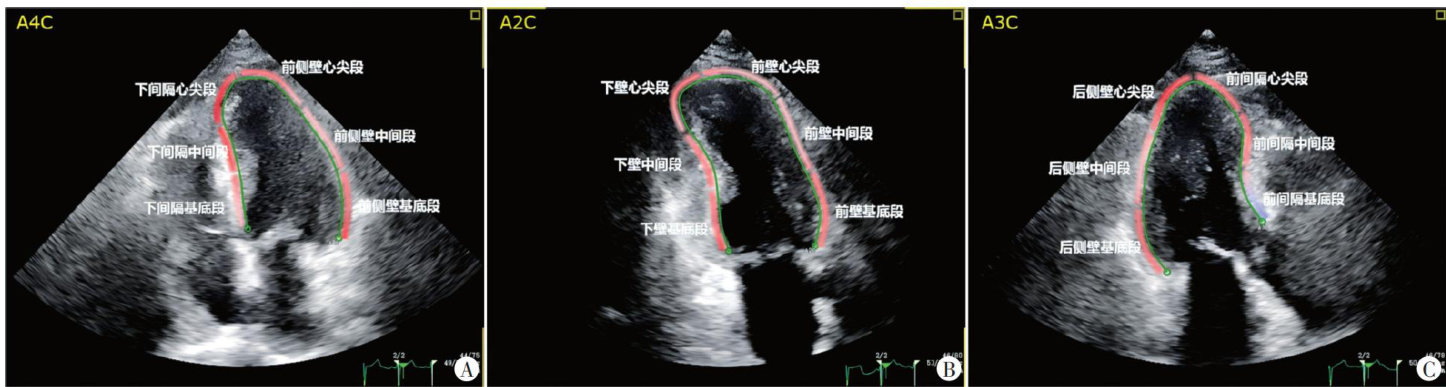

ABSTRACTObjectiveTo investigate the clinical value postsystolic shortening(PSS)parameters combined with quantitative flowratio(QFR)inpredicting the prognosis ST-segment elevation myocardialinfarction(STEMI)patientsafter percutaneous coronary intervention(PCI).MethodsAtotal104 STEMI patients whounderwentPCIinour hospital were enroled.Two-dimensionalspeckletrackingechocardiographywasperformedwithin24-48hafterPCItoobtainleftventricular PSS parameter[global postsystolic index(PSI)],earlysystolic lengthening parameter[global early systolic index(ESI)]and globalongitudinal strain(GLS).QFR wascalculated basedoncoronaryangiographyfindings.All patients were followed upfor 12-24 months and divided into the good-prognosis group( n =87) and the poor-prognosis group(n=17) according to the adverse cardiovascular events.The diferences intheabove parameters between thetwo groups were compared.Multivariate Logistic regression wasused toidentifyindependentinfluencingfactorsforpredictingtheprognosisafterPCIinSTEMIpatients,anda combined model was established.Receiveroperating characteristic(ROC)curve was drawn to analyze thediagnostic performance. ResultsCompared withthe god-prognosis group,theGLSinthe poor-prognosis group wasdecreased,and globalSI,global ESI,andQFR positivityrate were increased,with statisticallysignificant differences(all P <0.05).MultivariateLogistic regression analysisshowed thatGLS,globalPS,andQFRweretheindependentinfluencingfactorsforpredicting prognosisafterPCIin STEMI patients(all P <0.05).The combined model equationwas:Logit (P)= -0.075-0.342×GLS+0.214×globalPSI+2.134×QFR. ROC curveanalysisshowedthattheareaunder thecurvethe modelfor predicting prognosis afterPCIin STEMI patients was 0.928(95%CI: 0.871-0.985),with a sensitivity 82.0% and a specificity 89.0% .Conclusion The combined application PSS parameters and QFR has certain clinical value in predicting the prognosis after PCI in STEMI patients.

经皮冠状动脉介人治疗(percutaneous coronaryintervention,PCI)是ST段抬高型心肌梗死(ST-segmentelevationmyocardialinfarction,STEMI)患者的关键治疗方式,其可通过重建血运有效改善心肌缺血。(剩余10261字)